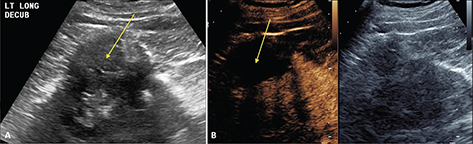

CEUS can be used to follow patients for residual or recurrent tumor with high accuracy. Any residual tumor will be identified as areas of increased enhancement. Absence of blood flow as in Figure 3B confirms complete ablation of the renal tumor. Note that it is not possible to determine if contrast is not utilized in Figure 3A. Figure 4 demonstrates a case where residual tumor (calipers) is present.

Fig 3

Figure 3. Successful ablation. Patient presented for 3-month post-RFA evaluation. (A) B-mode image before the ablation. Large heterogeneous tumor is noted on gray scale examination (arrow). (B) Absence of residual blood flow (arrow) is demonstrated on CEUS examination.

Fig 4

Figure 4. Tumor recurrence/inadequate ablation. Patient presented for CEUS examination 6 weeks after RFA. (A) The B-mode image demonstrates a complex mass (arrow) with solid and cystic components. It is not possible to determine if there is residual tumor. (B) CEUS image demonstrates the tumor (calipers) with residual flow in the posterior part of the tumor (arrow).